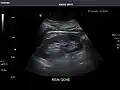

Renal ultrasonography

Ultrasonography of the kidneys is essential in the diagnosis and management of kidney-related diseases. The kidneys are easily examined, and most pathological changes in the kidneys are distinguishable with ultrasound.[7]

Kidneys: Right and left kidneys measure 11.5 cm and 12 cm in length respectively. No hydronephrosis. Small left lower pole kidney cyst.

Right kidney -